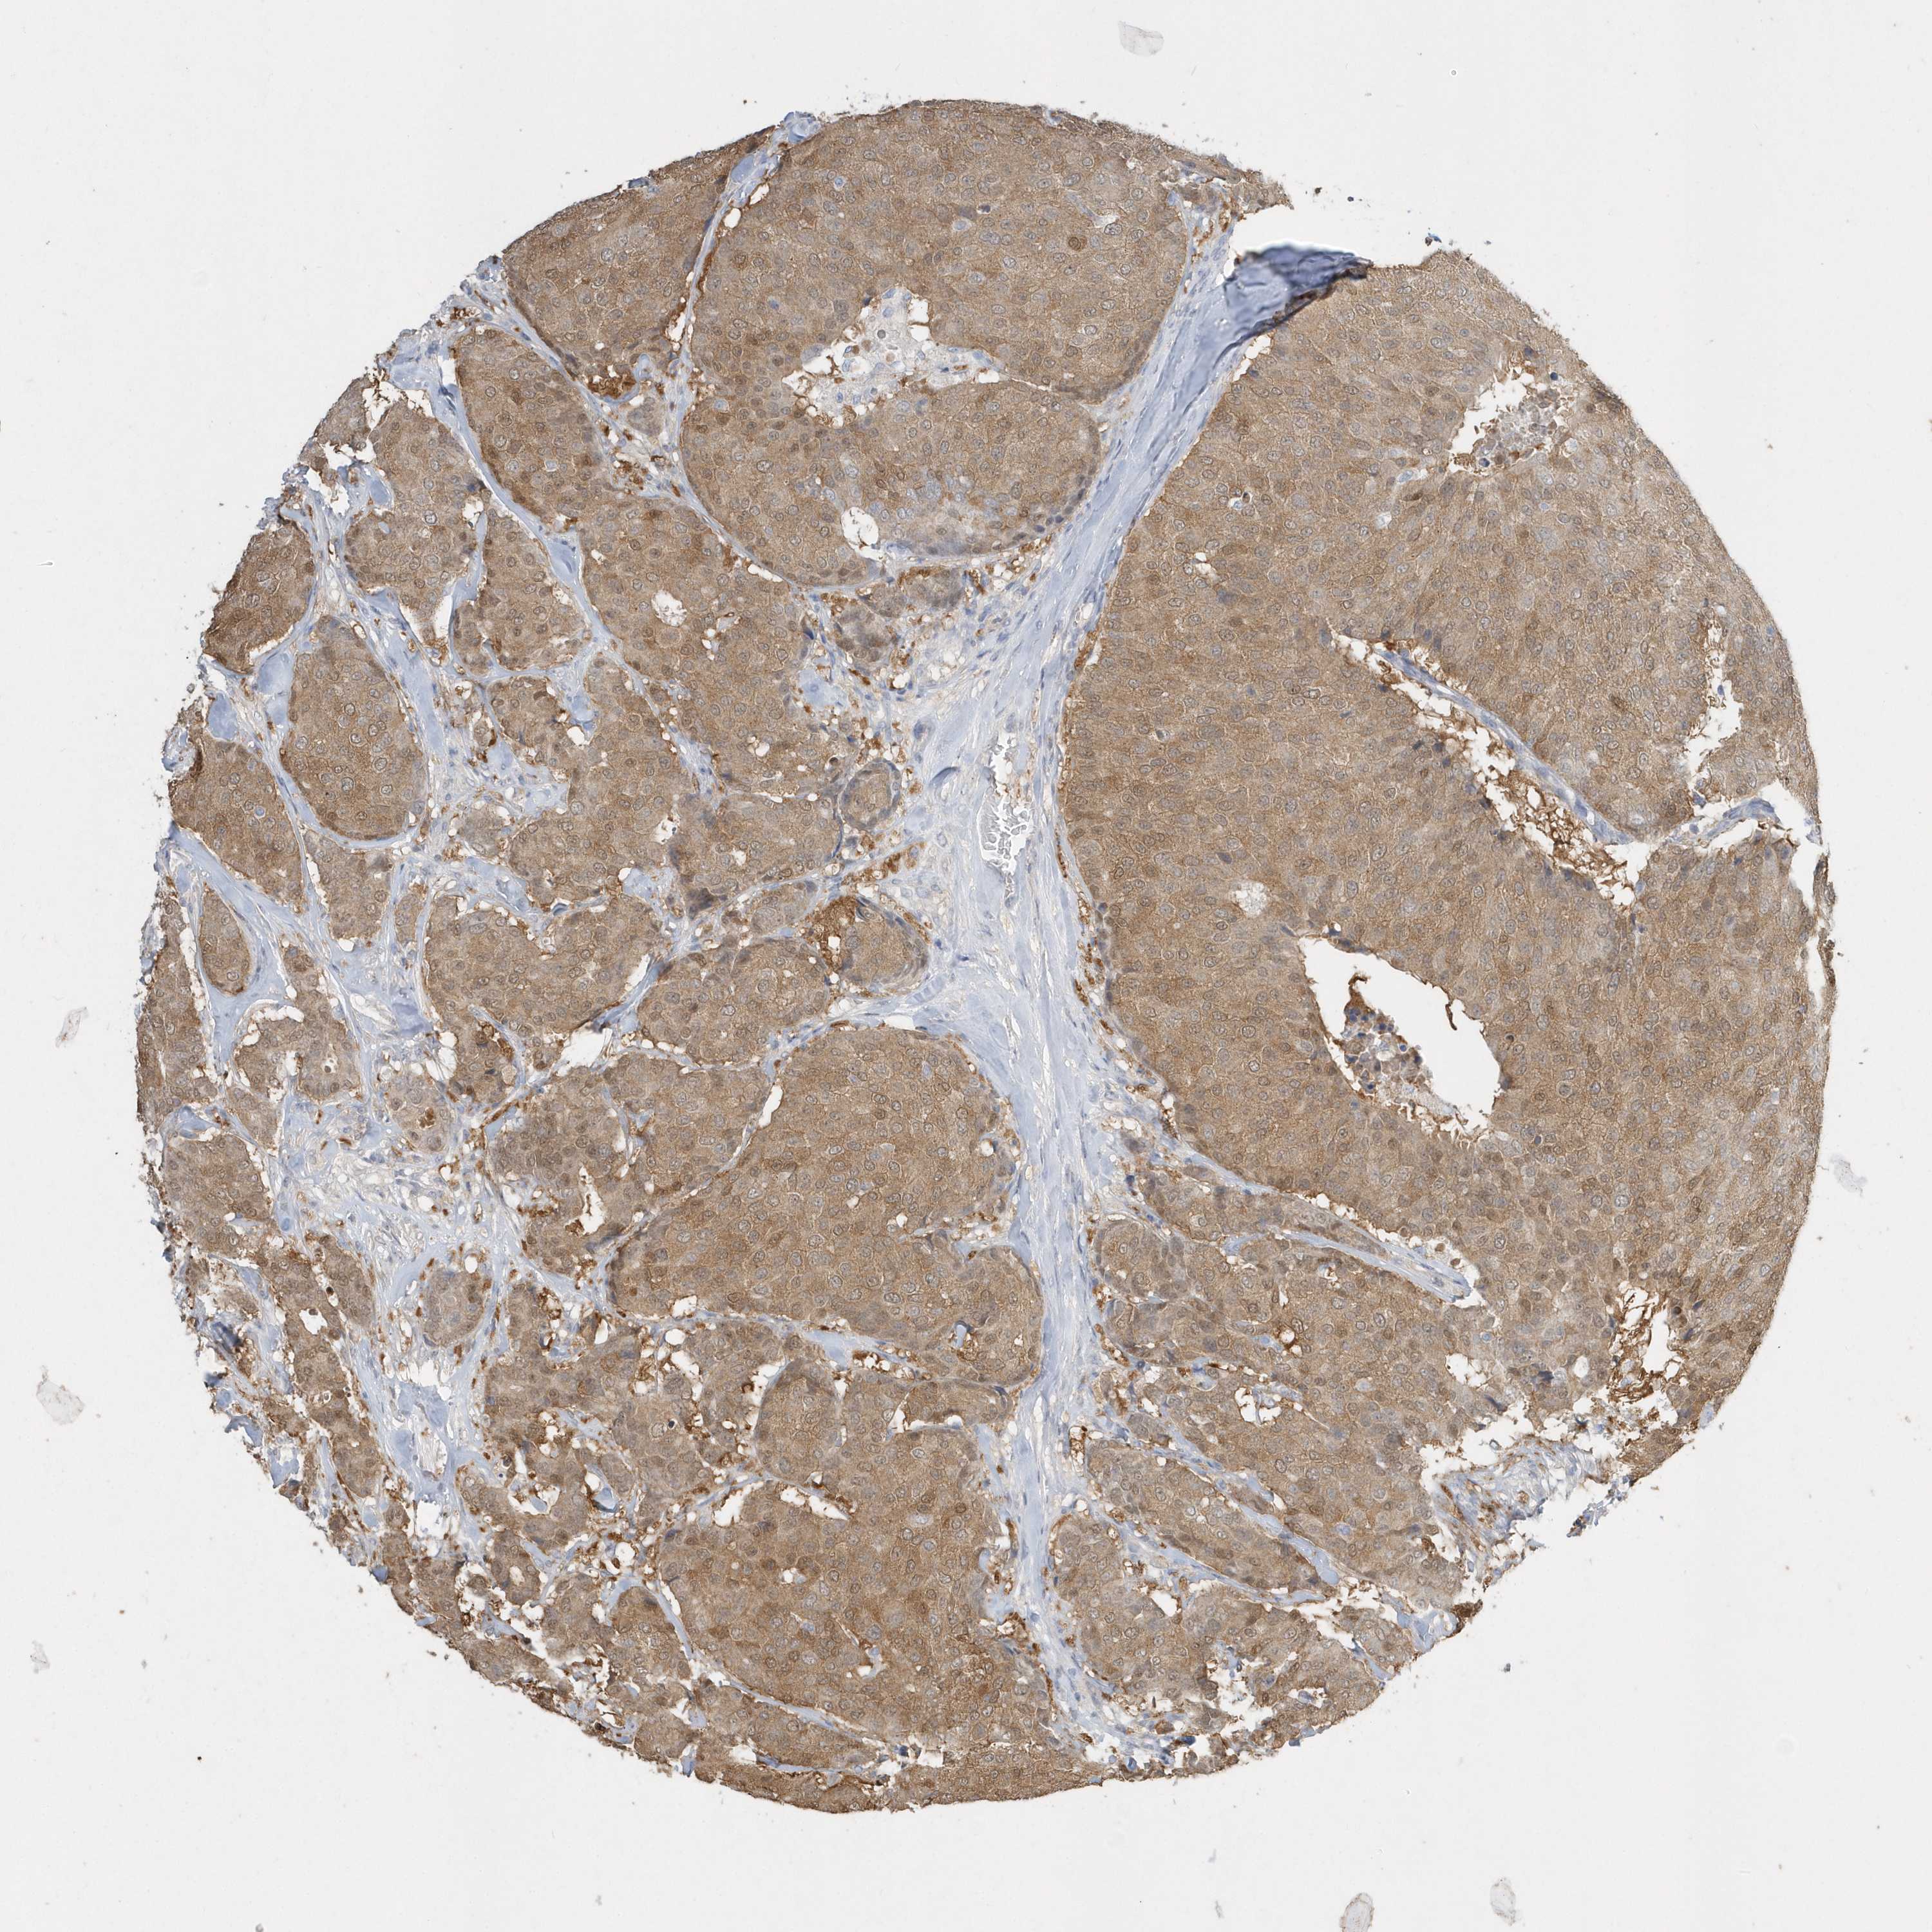

BRCA TCGA BRCA VALIDATION PROTEIN EXPRESSION